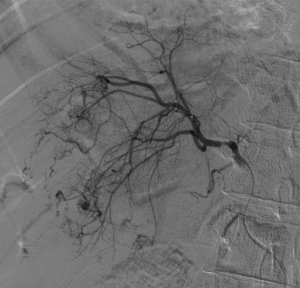

入院后,為患者給予補液,在局部麻醉下行DSA引導下經導管肝腫瘤動脈栓塞術。

肝癌破裂大出血并失血性休克患者往往病情急、危、重,如果治療不及時可能短期內死亡。未開展介入治療的醫院對此類患者只能給予輸血,補液,急診手術,在插管全麻下行開腹手術治療。但開腹手術往往切口長、手術時間長、手術創傷大,麻醉副作用大。可能術后出現肝功能衰竭,再出血,腹腔感染,切口疼痛,切口感染等并發癥。介入手術則往往較少出現這些并發癥。介入手術只需要在腹股溝穿刺一個2mm的小孔,置入導管到肝動脈,注入栓塞劑栓塞肝腫瘤的動脈,手術創傷小,止血可靠,除肝區疼痛及發熱外,較少出現其它并發癥,病人舒適度明顯提高,而且能早期進食及下地活動,恢復快,能縮短住院時間,具有療效好且微創的優點。